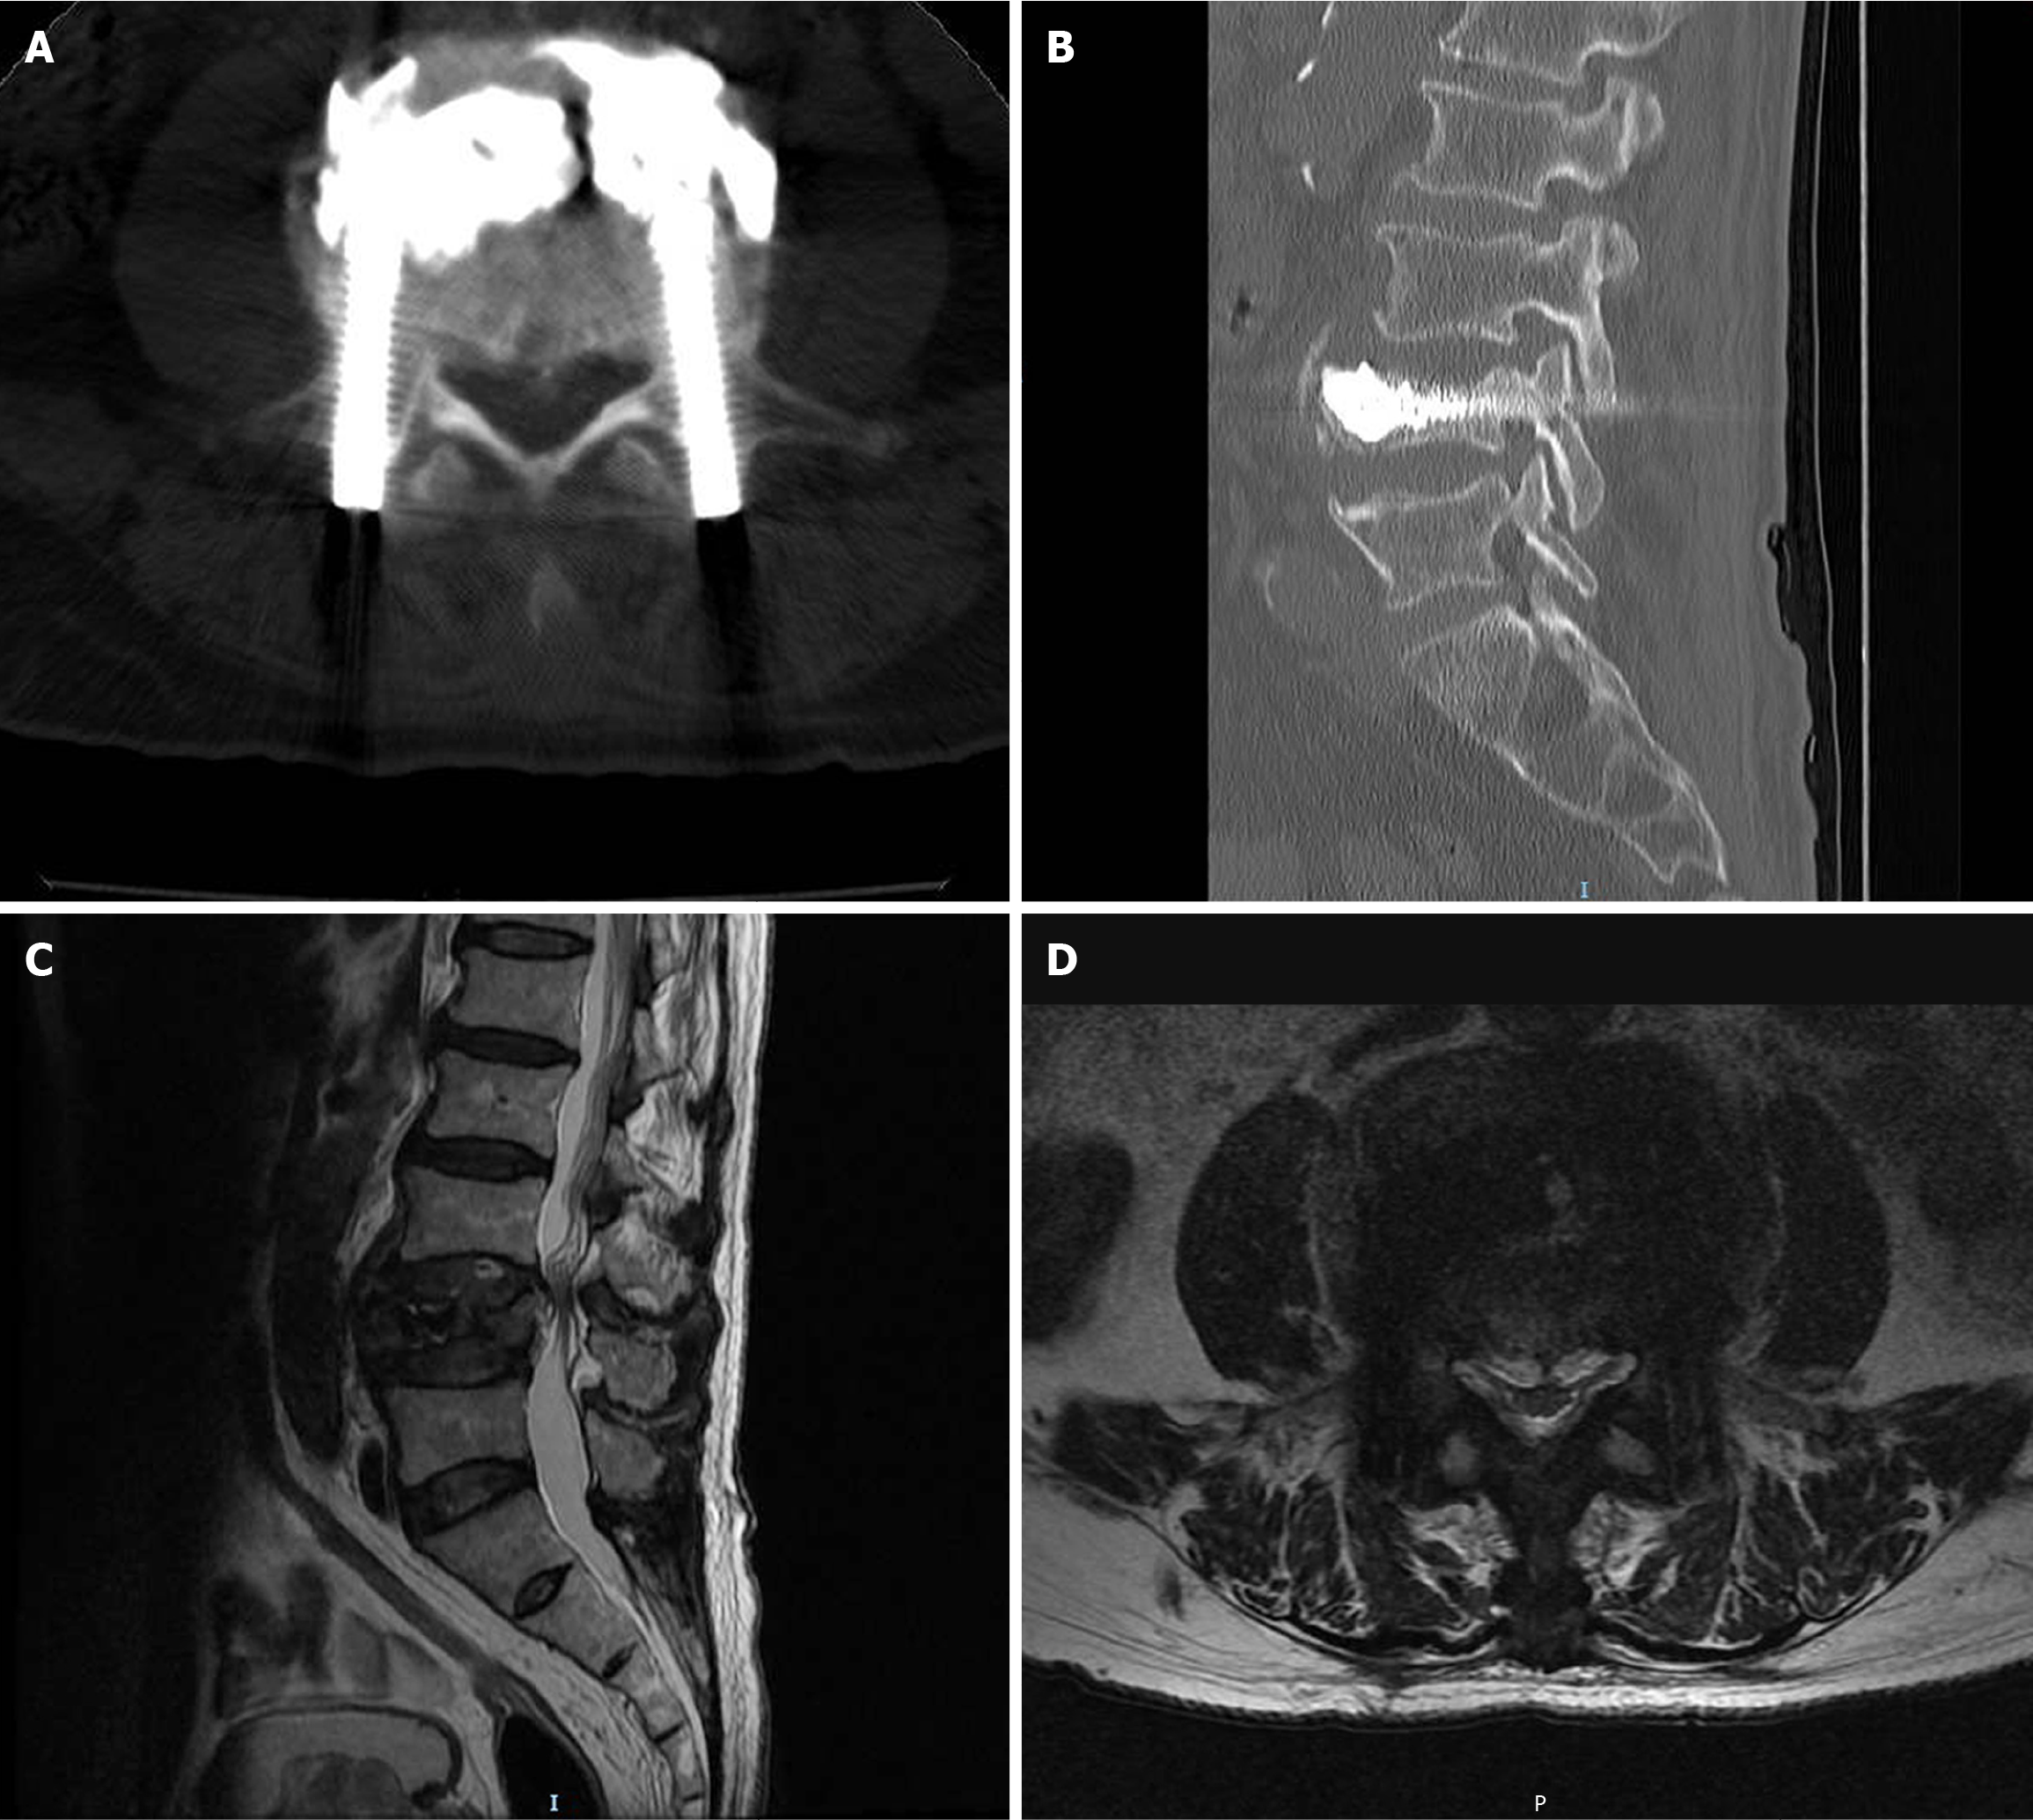

Figure 4 Lumbar computed tomography and magnetic resonance imaging images obtained at the follow-up examination three months after surgery.

A and B: Postoperative three-month lumbar spine axial (A) and sagittal (B) computed tomography images; C: Postoperative three-month sagittal short tau inversion recovery image of lumbar spine magnetic resonance imaging; D: Postoperative three-month lumbar magnetic resonance imaging transverse section image acquired at the lower margin of the L3/4 intervertebral disc level.